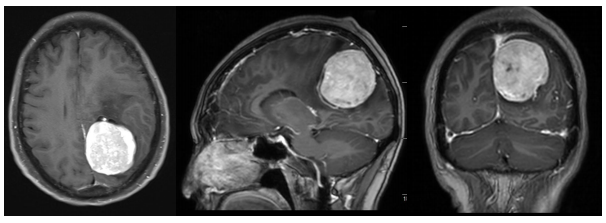

手术历时5小时,肿瘤被完整切除。术后病理报告显示为WHO I级过渡型脑膜瘤,也就是良性脑膜瘤。术后秦婆婆恢复顺利,意识清楚,四肢活动正常,复查头颅CT后确认肿瘤无残留,目前已成功康复出院。

图片3.png术后影像检查